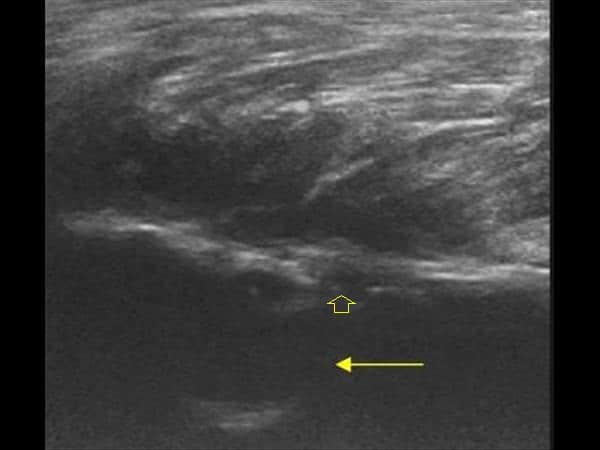

Apxe Brodie

Apxe Brodie + Mất liên tục màng xương

Apxe Brodie + Mất liên tục màng xương - Phù nề mô mềm

Viêm xương tủy

» Thông tin: Nam giới – 34 tuổi.

» Lâm sàng: Sưng đau khớp gối.

# Apxe Brodie / Mất liên tục màng xương – Phù nề mô mềm.